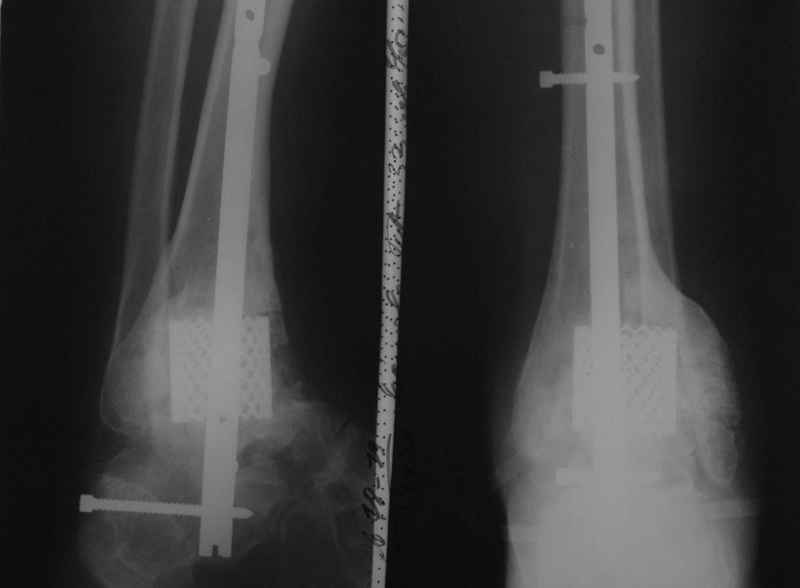

Пациентка Б. получила травму 2001 году в результате падения с высоты. За это время дважды выполнялись неудачные попытки артродезирования голеностопного сустава. Больная перед нами поставила одну задачу - восстановить опороспосонбность левой нижней конечности и только. Принято решение выполнить кейдж-артродезирование левого голеностопного сустава блокируемым интрамедуллярным гвоздем с установкой сетчатого опорного трансплантата, костной аутопластикой плюс Chronos. С целью профилактики рецидива деформации выполнили ахиллотомию (считаем, что неудачи предшествующих операций связаны с варусной тягой ахиллова сухожилия в ррезцльтате неправильно сросшегося перелома пяточной кости). На сегодняшний день - два месяца с момента операции. Пациентка перемещается в циркулярной повязке с полной нагрузкой на больную ногу.